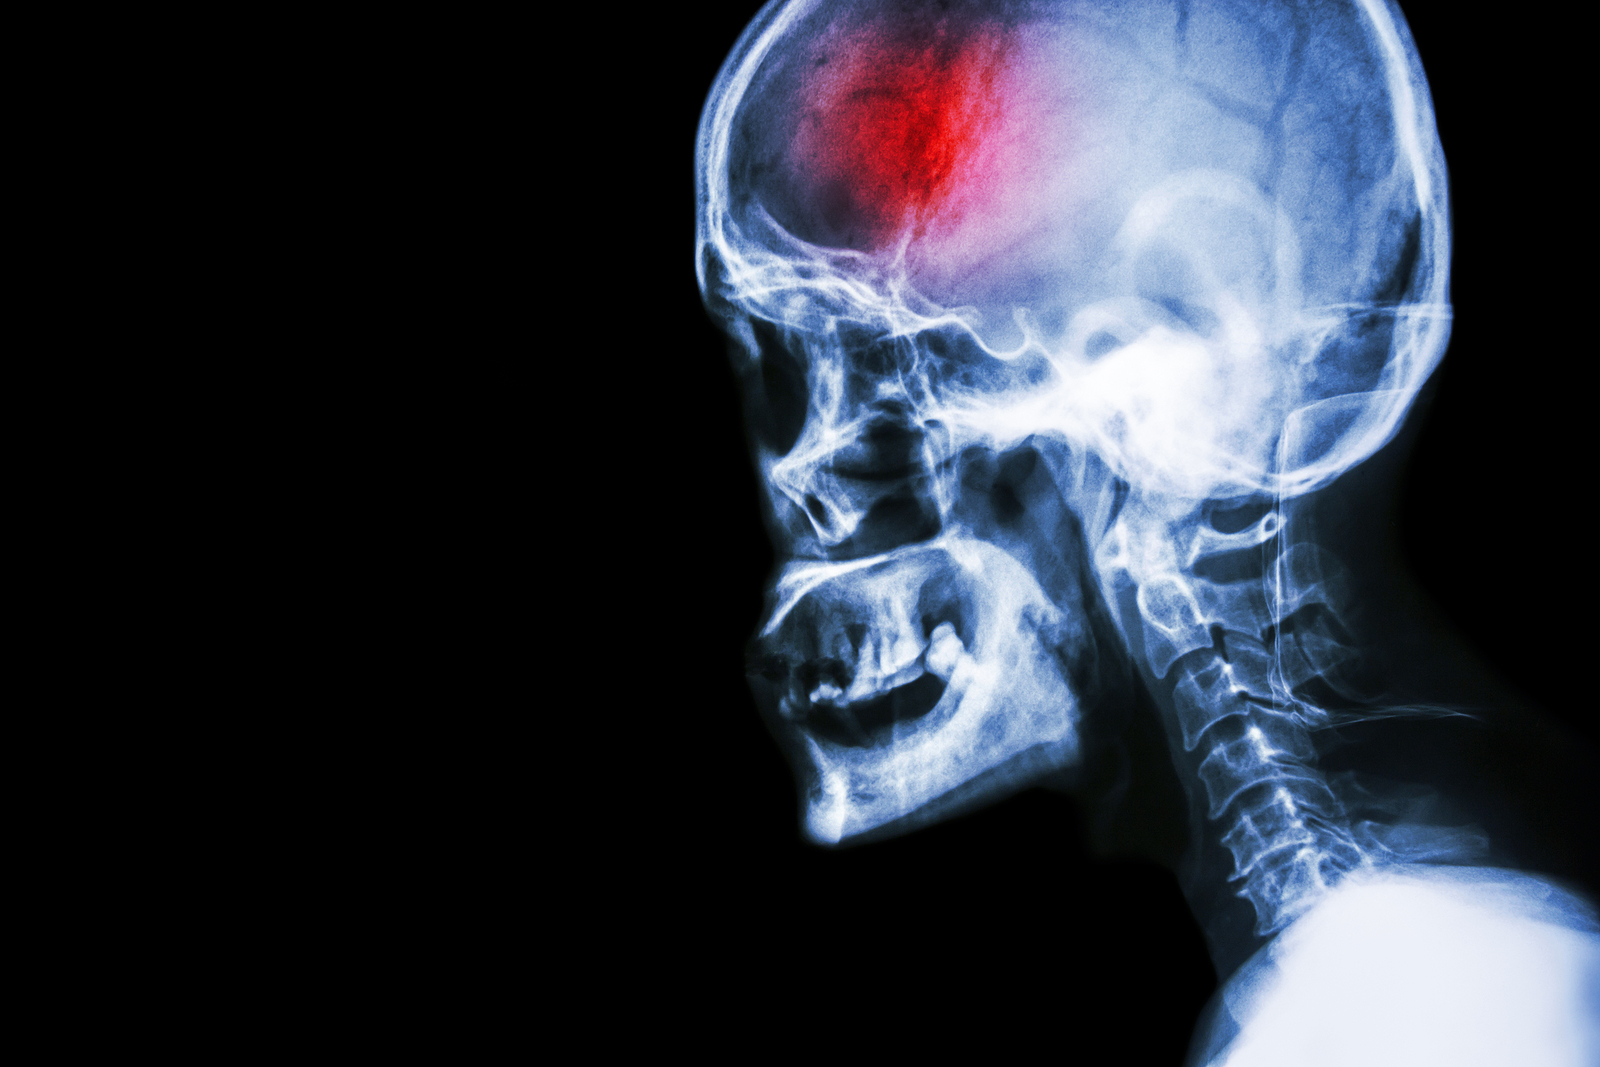

A stroke (previously known as a cerebrovascular accident) when there is a decreased flow of blood to the brain from either a blockage in the blood vessels that supply the brain (ischemic stroke), or a bleed from the blood vessels that supply the brain (hemorrhagic stroke). When the blood flow to the brain is blocked it prevents the brain from getting the needed oxygen and nutrients to function. Without oxygen the brain cells can be permanently damaged or die and the physical and mental functions related to that area of the brain will be affected. A stroke is a medical emergency and rapid treatment is crucial to decreasing the damage caused by a stroke.

- Ischemic stroke: a stroke that is caused by a blockage (clot) that disturbs the blood flow to the brain.

- Hemorrhagic stroke: a stroke that is caused by a bleed that disturbs the blood flow to the brain and puts pressure on the surrounding tissue.

Computed Tomography (CT) scan and/or Magnetic Resonance Imaging (MRI) scan: These tests are done on your brain and used to locate the exact location of the stroke and to determine if it has been caused by a blockage or a bleed. These tests can also help rule out other conditions that may be causing symptoms, such as an infection or a brain tumour

The effects of each stroke are unique depending on where the blockage or bleed occurs within the brain. The brain anatomy is similar in all individuals, so if a stroke occurs in the left side of the brain, the function of the right side of the body will be affected. If a stroke occurs in the right side of the brain, the left side of the body will be affected. If one side of the body is fully paralyzed, it is called hemiplegia. If one side of the body is only partially affected and shows weakness rather than paralysis, it is called hemiparesis.